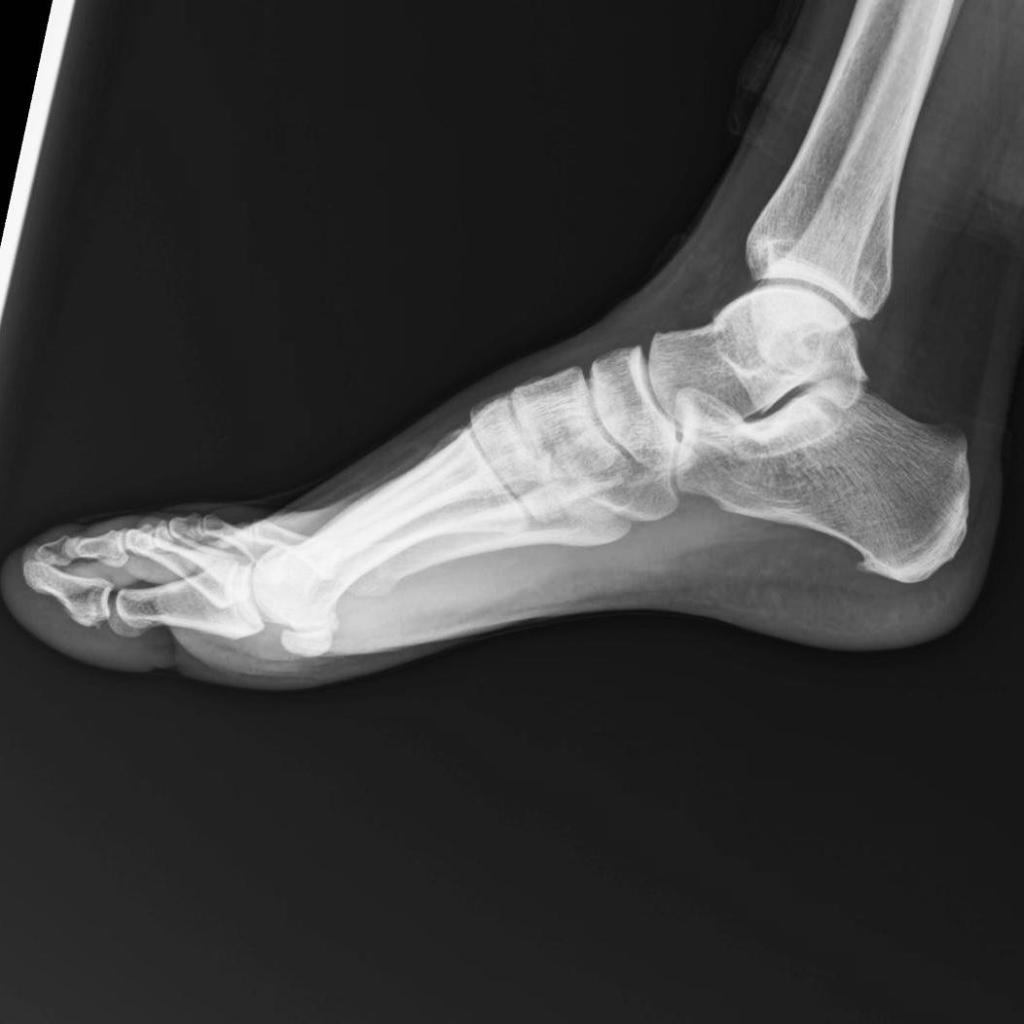

Ayer recibí los resultados de las placas que me hice en ambos pies… y para sorpresa de nadie, tengo espolón calcáneo en el pie izquierdo.

Yesterday I received the results from the X-rays I had done on both of my feet… and, to no one’s surprise, I have a heel spur in my left foot.